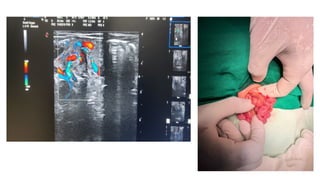

USG showing whirlpool sign of vessels which confirms

the presence of volvulus

14 DAYS MALE BABY OF BHAVANI

USG showing whirlpoolsign of vessels which confirms the presence of volvulus

14 DAYS MALEBABY OF BHAVANI